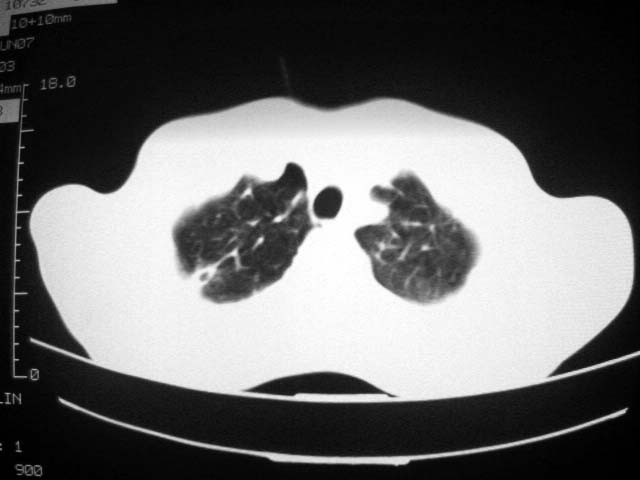

标题: CT7988D:近期图像 出乎意料!

从ct7988c 至今未用任何抗生素及抗痨药,维持保肝治疗。患者低热、咳血渐消失。

07年6月22号复查

前几次大家认为是转移癌,但此次复查病灶却明显吸收好转,不支持诊断。请大家讨论。[emb10]

bu不可思议,前三次都怀疑转移,但从这次的片子看仍有结节,就是比原来小